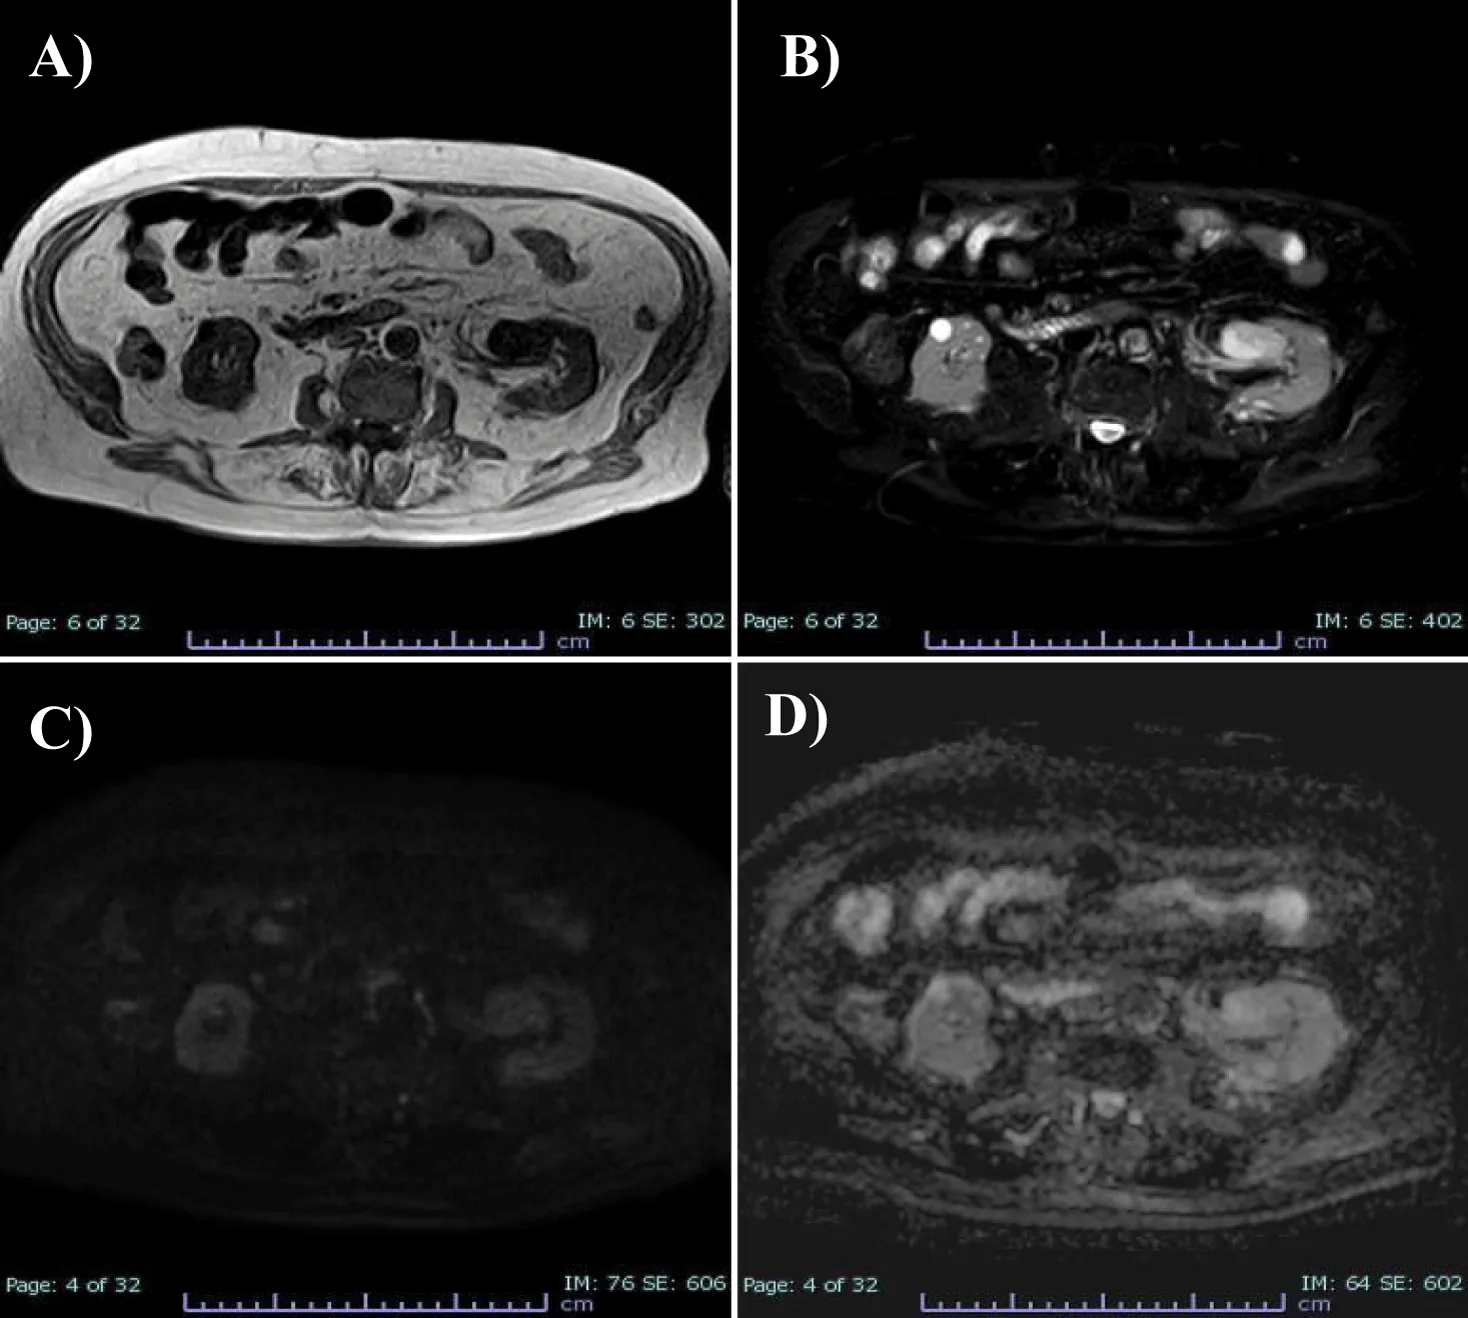

To better characterize the lesion, the patient underwent MRI examination of the upper and lower abdomen without and with intravenous CM (Figure 2).MRI images showed T1-dependent signal hypointensity (Figure 2A), inhomogeneous T2-dependent signal hyperintensity (Figure 2B), and appears to have poor diffusion-weighted signal restriction (Figures 2C,D). Overall, it is characterised by inhomogeneous contrast impregnation and has a greater axis of 32 x 23 x 26 mm (LL x AP x CC). This technique confirms that the heteroformation did not generate compressive effects on the renal pelvis or vascular invasion. No significant mesenteric, para-aortic or retroperitoneal lymphadenopathy was evident.

MRI images also show characteristics of inhomogeneous signal intensity, reflecting its vascular nature, revealing signal hypointensity in T1 sequences, inhomogeneous signal hyperintensity in T2 and poor signal restriction in DWI, indicative of poor cellularity. The final histopathological result was Anastomotic hemangioma, a benign entity associated with an excellent prognosis [8]. There are no reports of metastasis or recurrence after nephrectomy. However, it is still controversial whether total nephrectomy is necessary for such benign lesion [8].